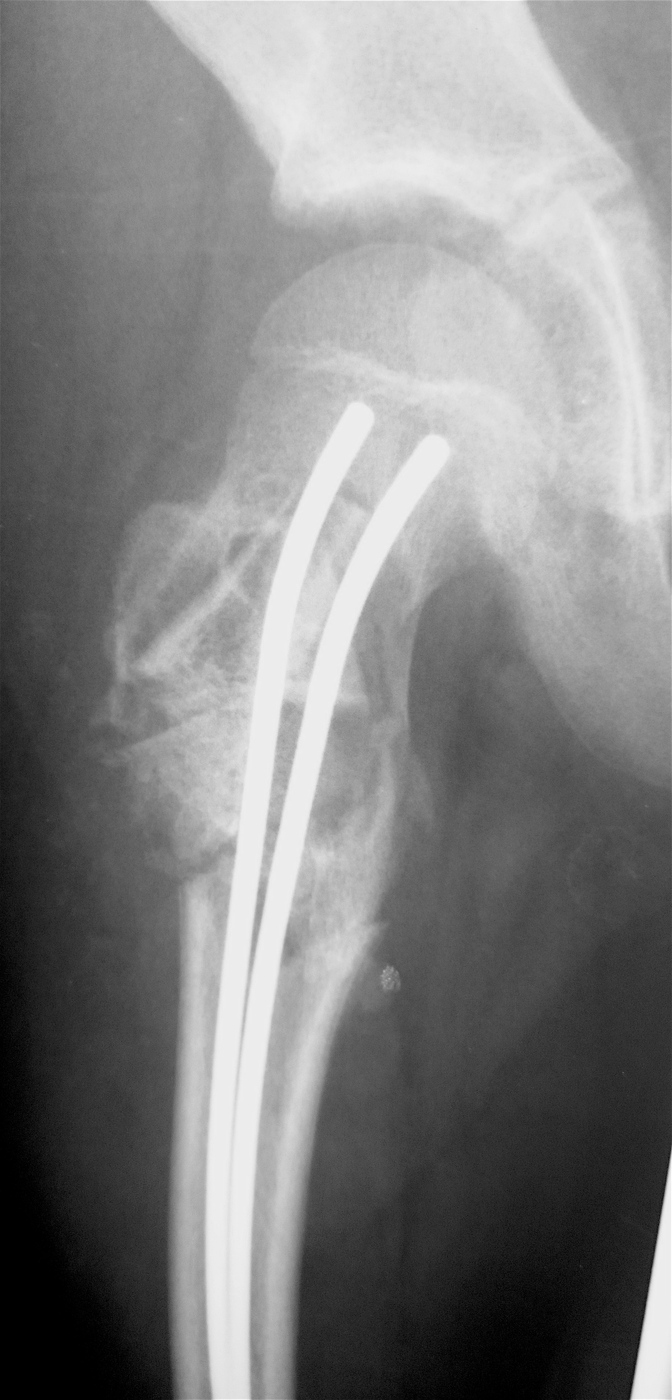

Закрытый, паталогический перелом в подвертельной области правой бедренной кости со смещением, на фоне аневризмальной костной кисты.

Выполнена резекция с аллопластикой губчатыми и кортикальными биоимплантатами "Лиопласт".